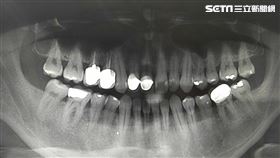

做根管治療 醫警:沒做好恐從頭來過

不少人因為嚴重蛀牙,需要進行被稱為「抽神經」的根管治...